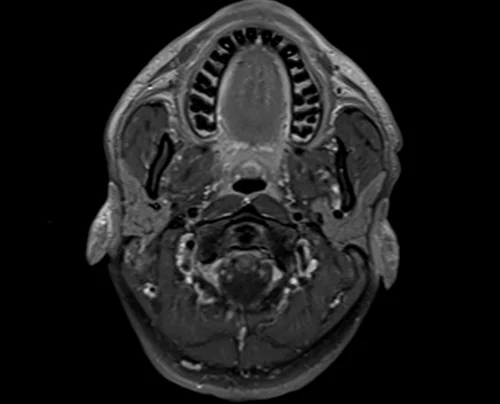

MRI Soft tissue neck axial T1 fat sat post contrast images